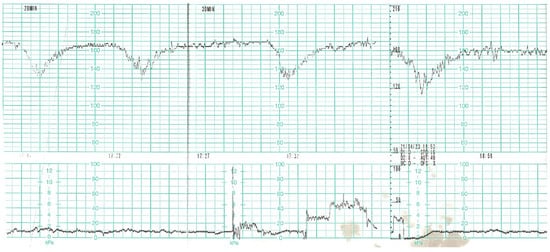

On the day of caesarean section, the patient’s vital parameters were: BP 130/80 mmHg, HR 110 bpm, Sat. 96%, breaths 20/min. Laboratory tests showed persistent abnormal clotting parameters. The drainage from the pelvis was 800 mL of blood, and in the control abdominal ultrasound examination the subcutaneous haematoma was observed. Due to the above, the patient was qualified to the relaparotomy and pelvic revision. During the procedure, another 2 g of fibrinogen, 2 units of platelet concentrate and 2 units of packed red blood cells were given. During the next two days, the patient was monitored in a postoperative room. Stable laboratory test values were obtained. Table 1 summarises the results of the patient’s examinations. A CT scan of the chest was performed. Massive converging zones of bubble densities in the type of frosted glass and paving stones, suggesting viral inflammation (typical for SARS-CoV-2 infection) were visible—see Figure 4 and Figure 5. Due to the gradually increasing respiratory failure (saturation 90%, and hypoxia—pO2 54 mmHg in a control arterial probe), high-flow nasal oxygen therapy was started. The satisfactory effect was not achieved. Sedation, intubation, and mechanical ventilation was initiated. After initial stabilisation the patient was transferred to the Intensive Care Unit, where she stayed for 8 days until improvement in oxygenation was achieved. She was successfully extubated and transferred to the Maternity Ward, from where she was discharged on the 22nd day of hospitalisation in good general condition.

Figure 4. Chest Computed Tomography (HRCT).

Figure 5. Chest Computed Tomography (HRCT).